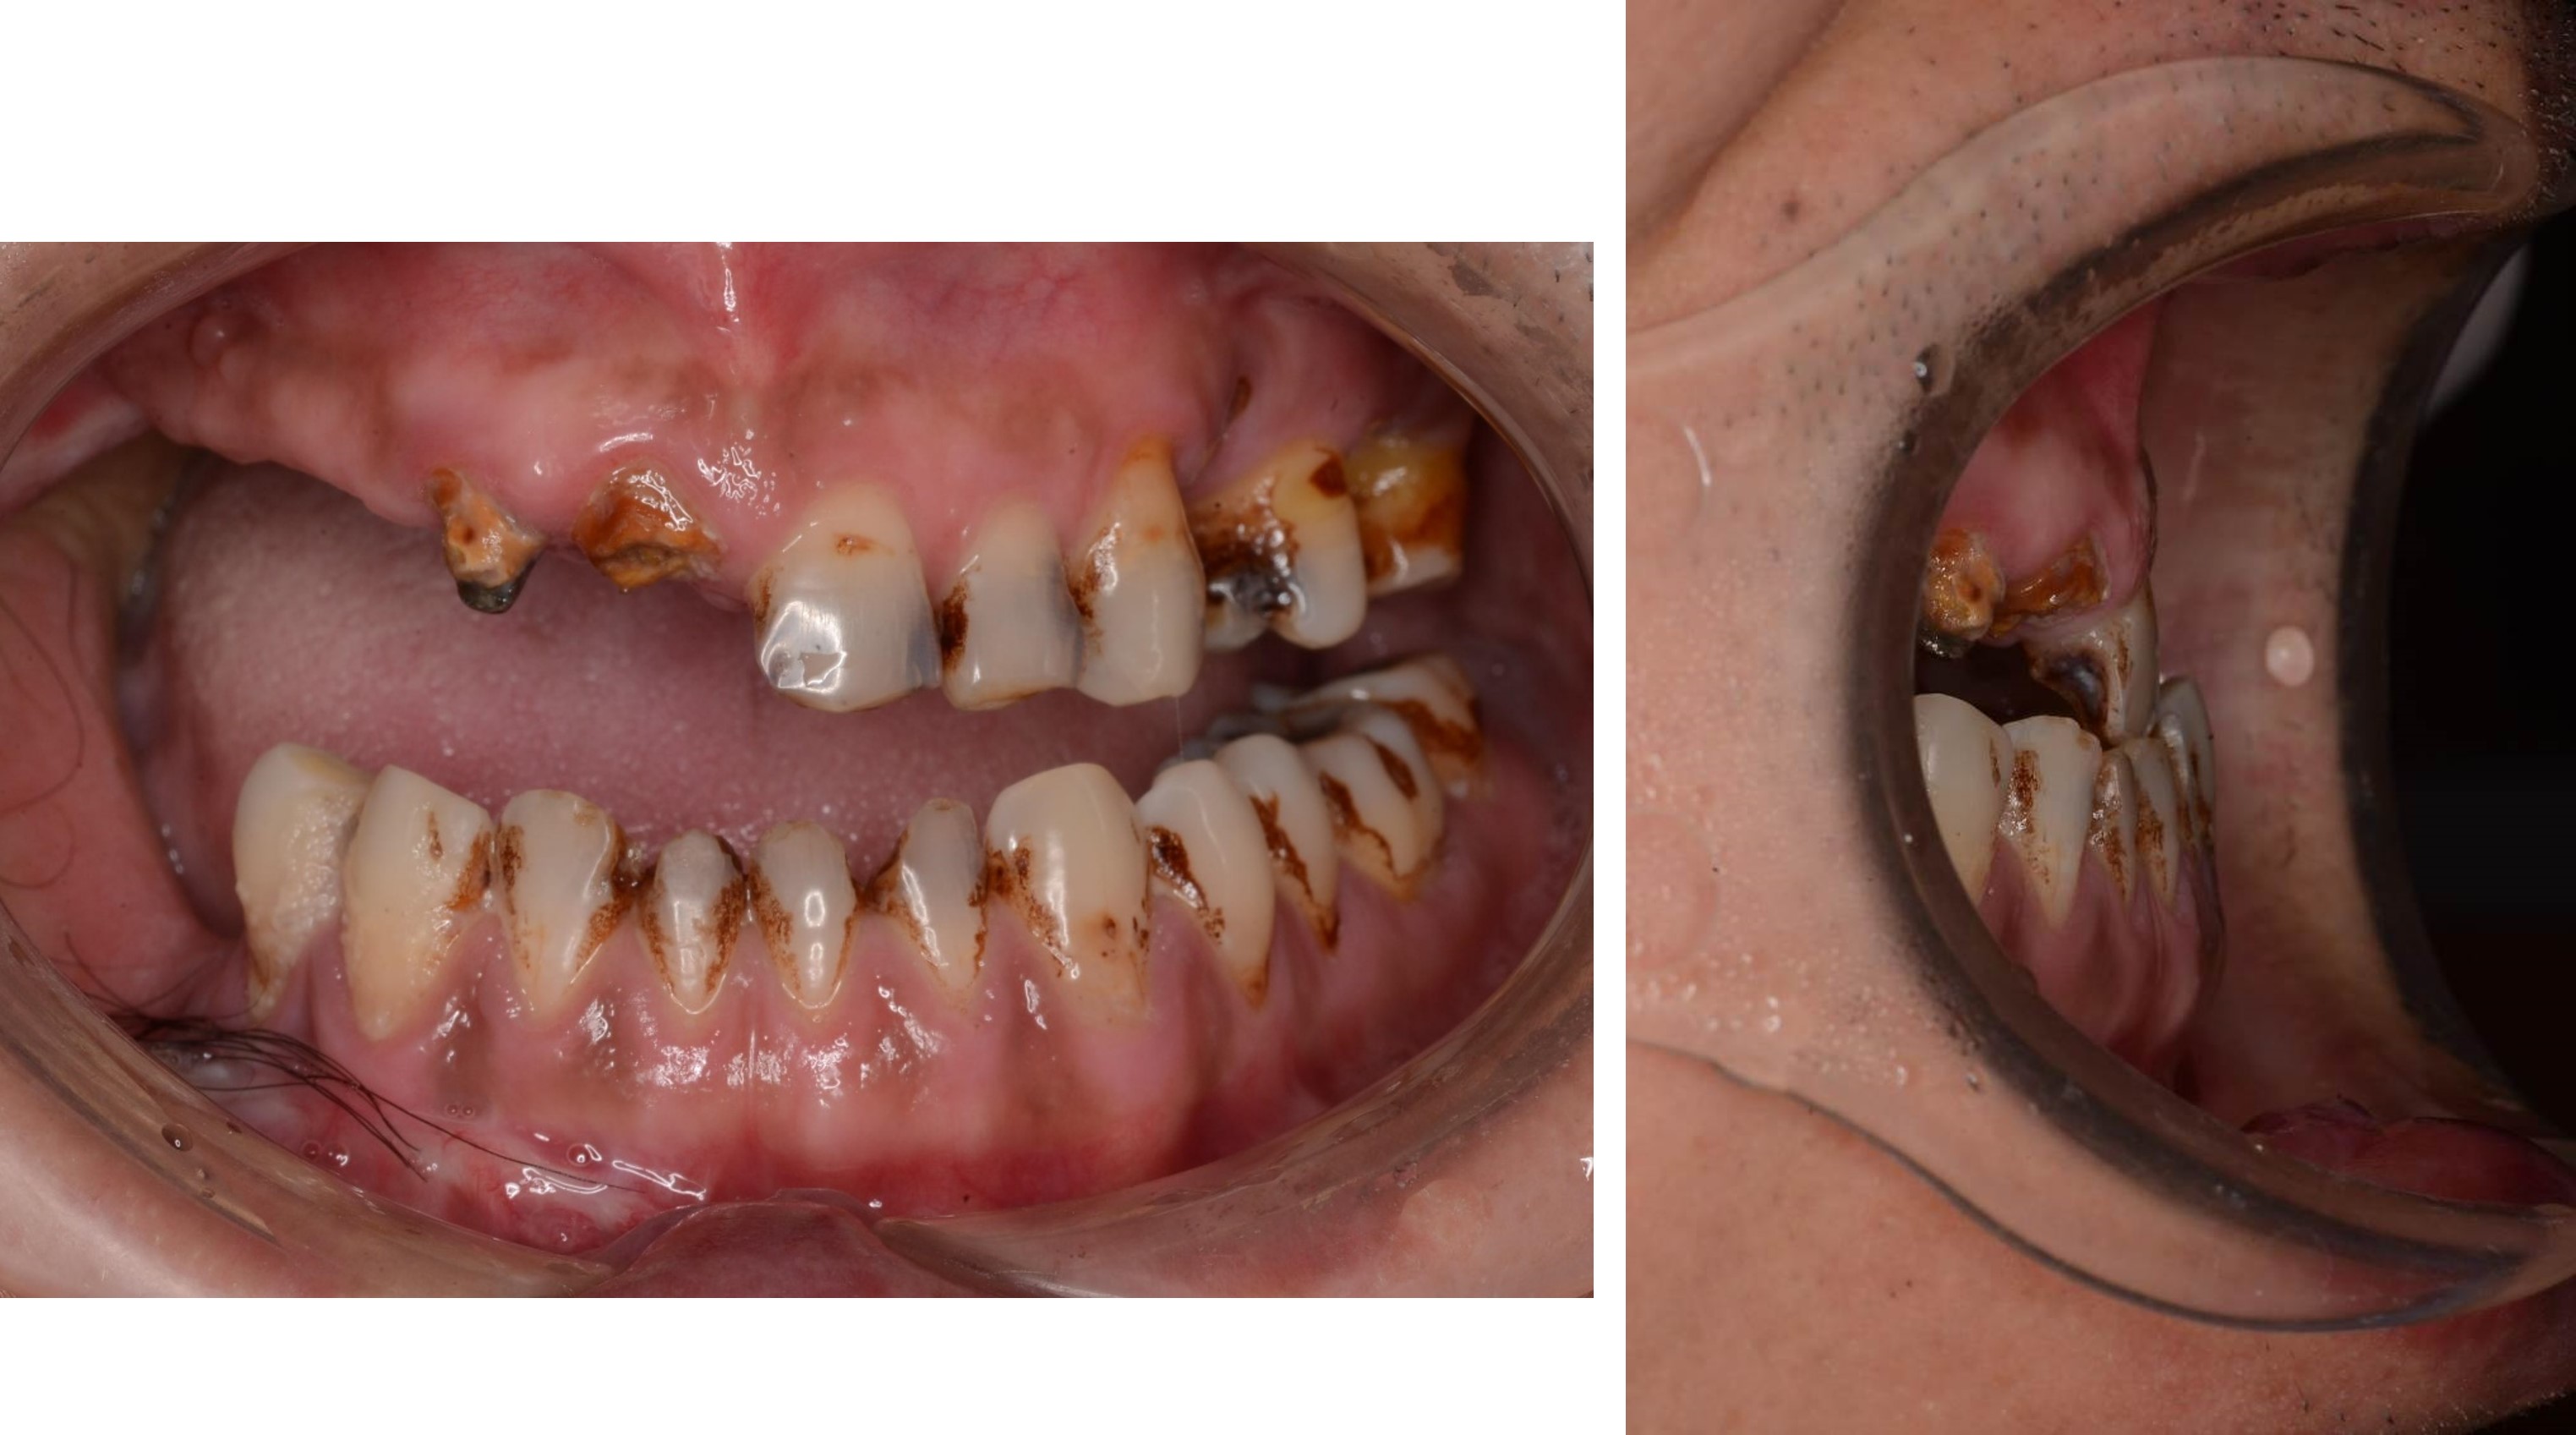

治療前上下顎因口外手術,造成咬合喪失

治療前,咬合喪失,磨耗

治療前,殘根與牙周支撐不良